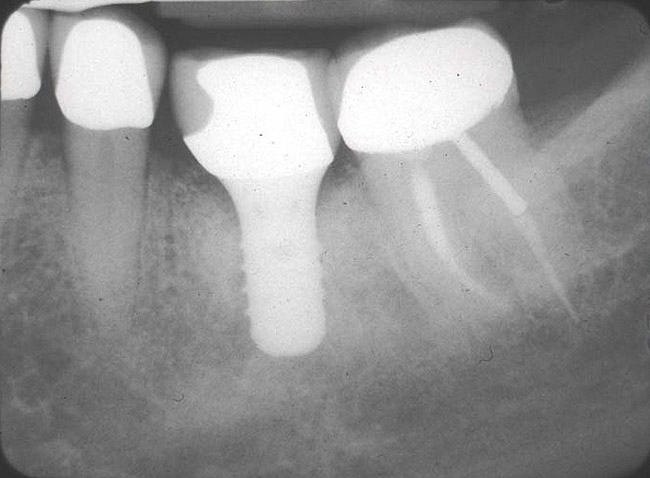

If the most crestal aspect of the interradicular bone is at least 3-mm-wide mesio-distally: A 2.2-mm-wide guide bur is drilled to the appropriate length, a guide pin is inserted, and a radiograph is taken (Figure 7). If necessary, the initial osteotomy is extended apically. A tapered osteotome is inserted into the osteotomy and moved mesio-distally and bucco-lingually to expand the osteotomy site. A 2.8-mm bur is used to prepare the osteotomy to depth, and a 2.8-mm-wide tapered osteotome is inserted in the osteotomy and once again utilized in mesio-distal and bucco-lingual directions to expand the osteotomy site. If the mesial and distal aspects of the interradicular bone are still intact at this point, a 3.5-mm bur is utilized to prepare the osteotomy to depth. A 3.5-mm-wide osteotome is inserted into the osteotomy and utilized in the manner already described. A decision is made as to whether to place a tapered implant with a 4.1-mm-wide base and a 6.5-mm-wide neck, or to use a 4.8-mm-wide bur and prepare the osteotomy to depth, in anticipation of placement of an implant with a 4.8-mm-wide parallel wall body and a 6.5-mm-wide platform. The chosen implant is inserted into the osteotomy (Figure 8), appropriate regenerative materials are placed, and the flaps are sutured. Following maturation of the regenerating hard tissues, the implant is ready for restoration (Figure 9). A radiograph taken 54 months after implant restoration demonstrates stability of the peri-implant crestal bone (Figure 10).

Case reports of these techniques can be seen in Figure 11 through Figure 19.